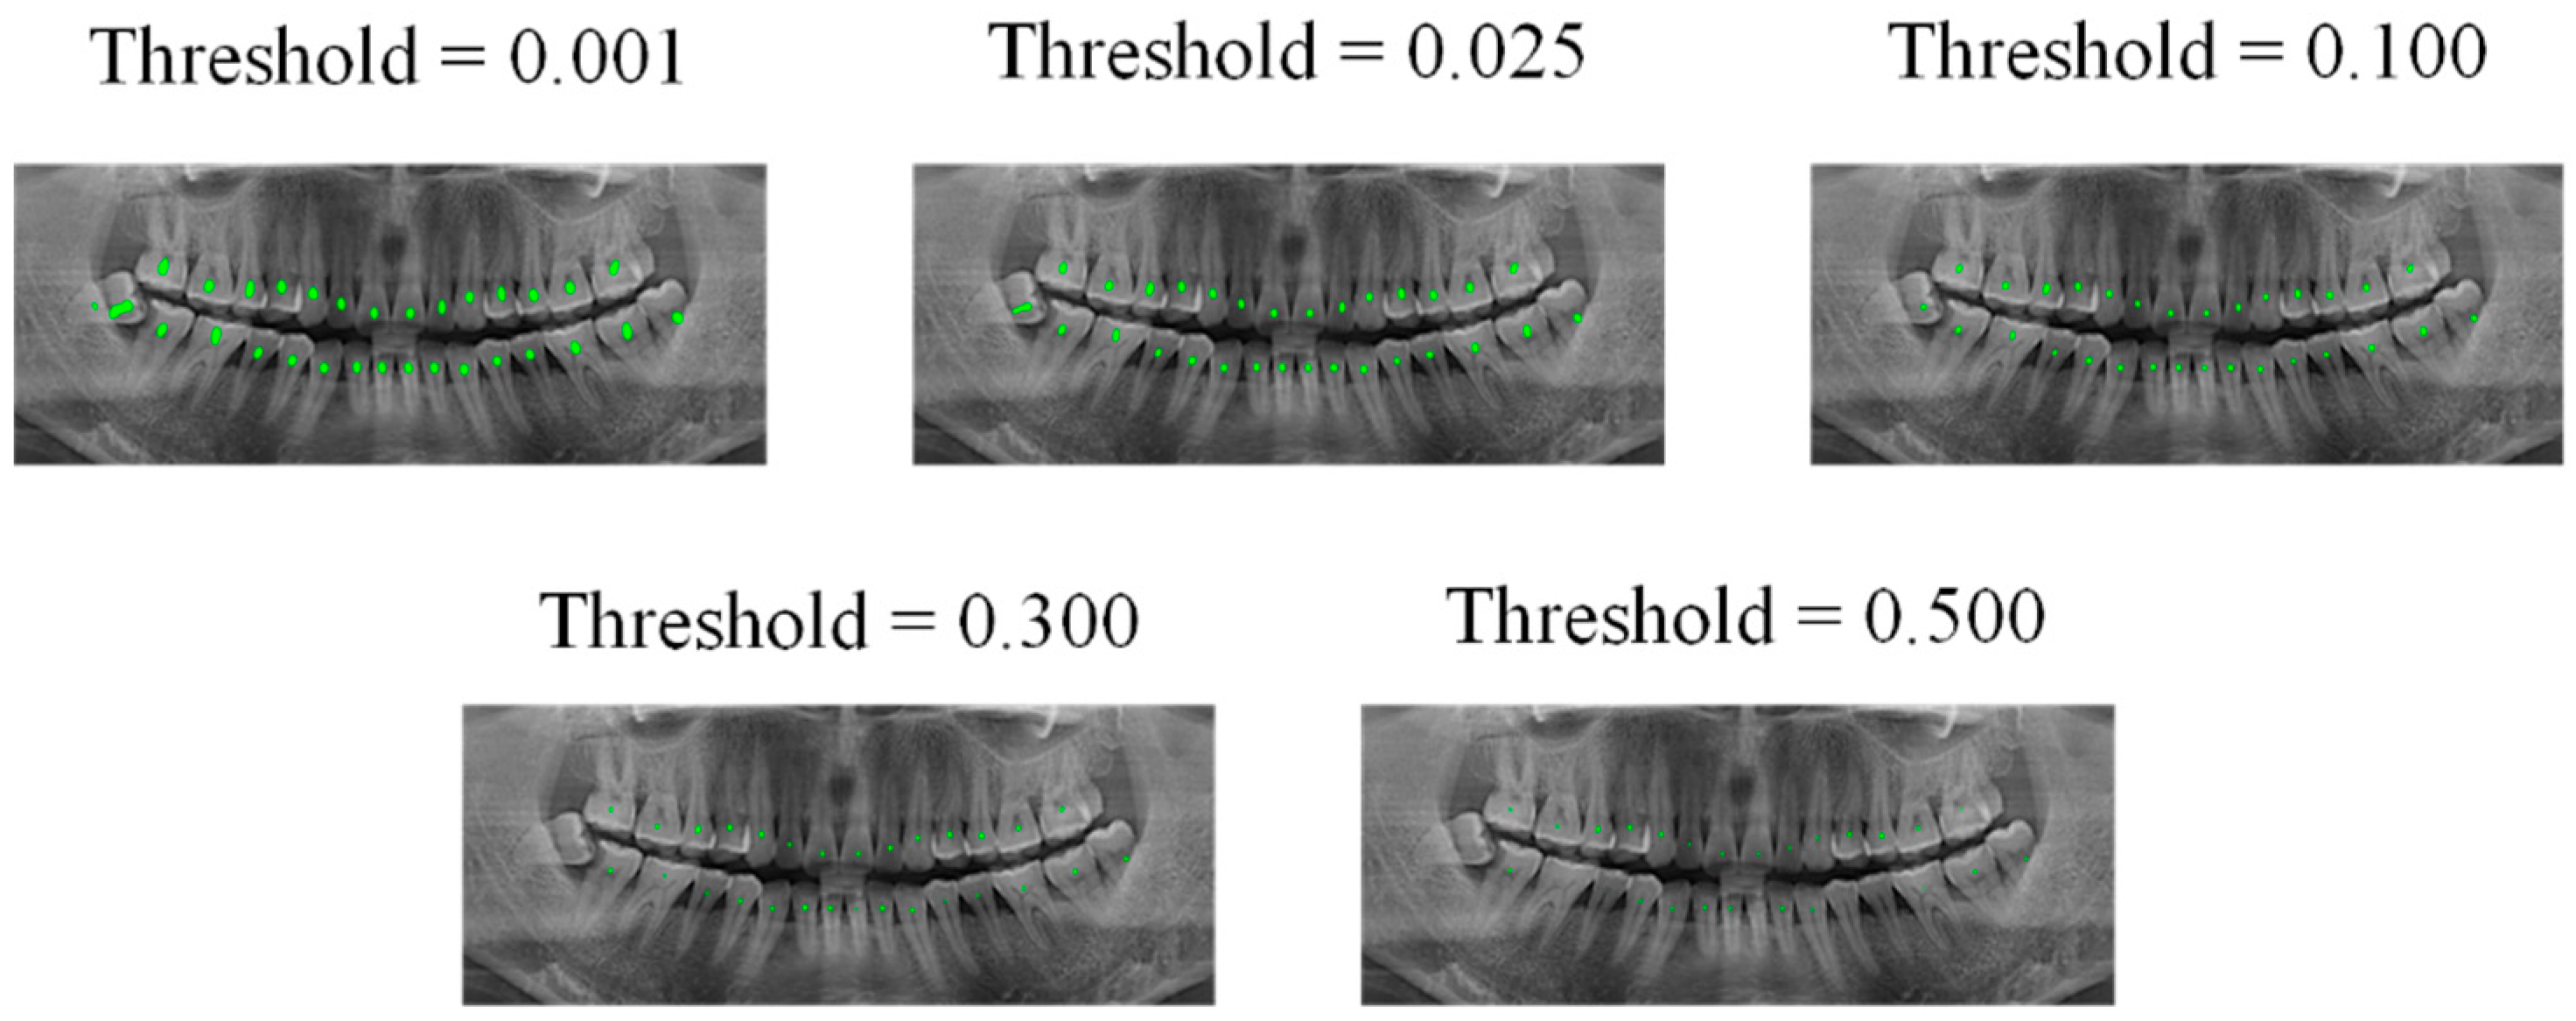

Subsequently, two deep learning models were trained using datasets A and B; both models were U-Net, and due to our hardware limitations, we set the batch-size to 1, the learning rate to 0.01, and the epochs to 9. Then, we input the 10 processed images into the model trained in dataset B to obtain 20 edge images with threshold values of 0.5 and 0.94, and used the channel stitching method to stitch these edge images with the semantic segmentation mask, to obtain 20 processed images. In the next step, the VIA tool was used to mark the central points of these 20 images, perform image augmentation, and mark it as dataset C. Dataset C was used for training the new U-Net model. The effects of the measured model at output thresholds of 0.001, 0.025, 0.1, 0.3, and 0.5, are shown in Figure 10.

Figure 10.

Output of teeth central point dataset under different thresholds.

Figure 10 indicates that if the image output is according to the default output threshold (0.5) of conventional semantic segmentation, the central point image cannot effectively express all object centers of the teeth. However, if the output threshold is set to very low levels, we often encountered adhesion of the object centers of the teeth; based on experience, we set the threshold of the central point output to 0.025, so that all centers can be expressed as much as possible, and they are also well separated.